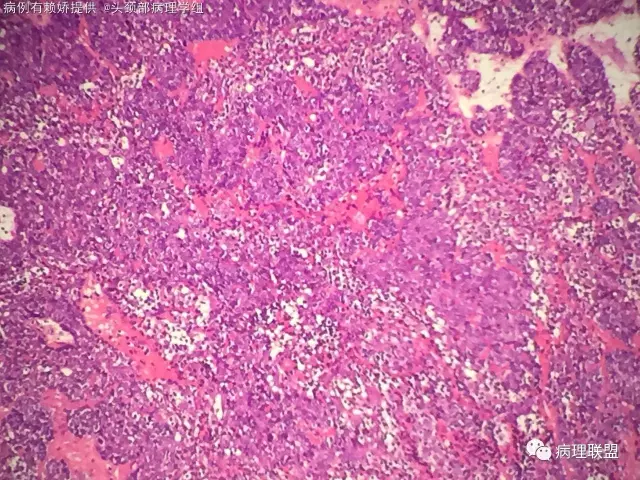

男,54岁,后颈部肿块10年(病例由赖娇 提供,致谢!)

小汗腺螺旋腺瘤

@梅宜兼 本例明显呈上皮巢排列,肿瘤由两种细胞构成外层呈栅栏状排列细胞小核染色深,另一种为咯略大淡染隐约可见小核仁的腺上皮细胞!间质可富裕血管,水肿及少量基底膜样物质!另外还有个特点散在淋巴细胞!该肿瘤肉眼看切片给人第一印象像个淋巴结!